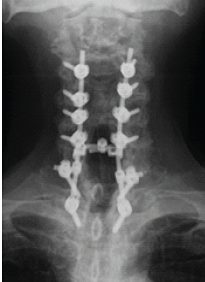

Chronic Irreducible C1–C2 Rotatory Subluxation Presenting as Painful Torticollis in a Child Managed with Posterior Lateral Mass Fixation: A Case Report

Sachlang Debbarma , Chirag Sharma , Ajoy Baishya , Tashi G Khonglah , Bhaskar Borgohain , Sharat Agarwal

………………………………p.119-122